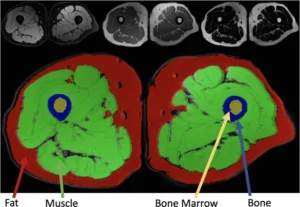

Musculoskeletal MR Image Segmentation with Artificial Intelligence

Authors: Keles, E., Irmakci, I., Bagci, U.

Advances in Clinical Radiology

Publication Year: 2022